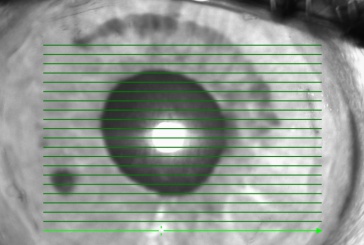

IOL tilt can be measured with ultrasound, the Purkinje reflection device, the Scheimpflug camera, anterior segment OCT, or subjective grading at the slit lamp with findings including transillumination defects.

Anterior segment optical coherence tomography (OCT)

Anterior segment OCT is a fast, noninvasive, non-contact and high-resolution method of measuring IOL tilt. The eye is scanned at the rotated axis which passes through the anterior corneal center and the pupillary center [1]. Advantages are the ability to be performed in the immediate postoperative period and in eyes with corneal opacification, such as from corneal edema, and it also does not need coupling fluid. The disadvantage is inability to visualize the haptic below the iris [9] [10].